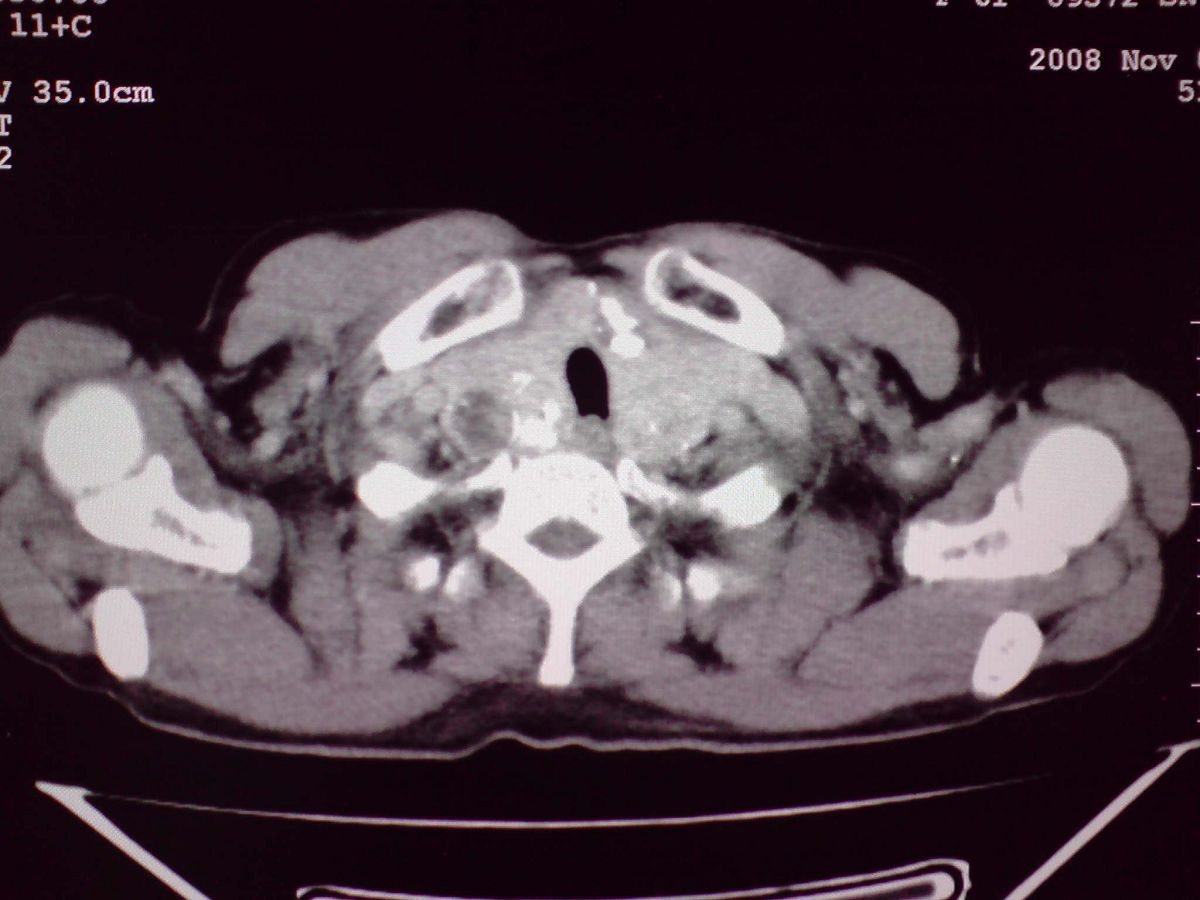

患者女性,65岁,无明显不适,甲状腺功能无异常

双侧甲状腺肿大,向下部分突入胸腔,双侧甲状腺内密度不均,可见结节状低密度影,并见散在斑点状钙化,增强后病灶实性部分强化明显,气管受压稍变窄左移。

考虑:双侧甲状腺腺瘤可能,不除外甲状腺癌。

甲状腺左右叶增大,并向下突入胸腔内,其内可见多发条片状钙化影及囊性低密度影,邻近组织及血管无浸润、包埋征像,双侧结节性甲状腺肿伴右侧甲状腺腺瘤形成可能性大,甲状腺癌待排;因病人就要手术,期待结果。